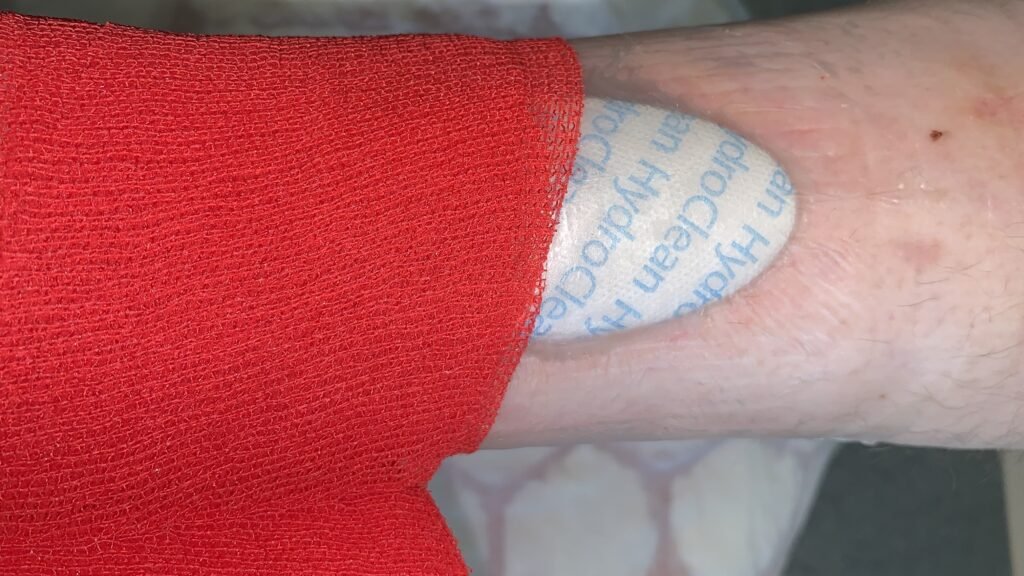

Sorbalgon Classic ![]() P und Sorbalgon T Classic sind tamponierbare, wirkstofffreie Kompressen und Tamponadestreifen aus Calciumalginat-Fasern. Keime werden während der Umwandlung in der Gelstruktur eingeschlossen.

P und Sorbalgon T Classic sind tamponierbare, wirkstofffreie Kompressen und Tamponadestreifen aus Calciumalginat-Fasern. Keime werden während der Umwandlung in der Gelstruktur eingeschlossen.